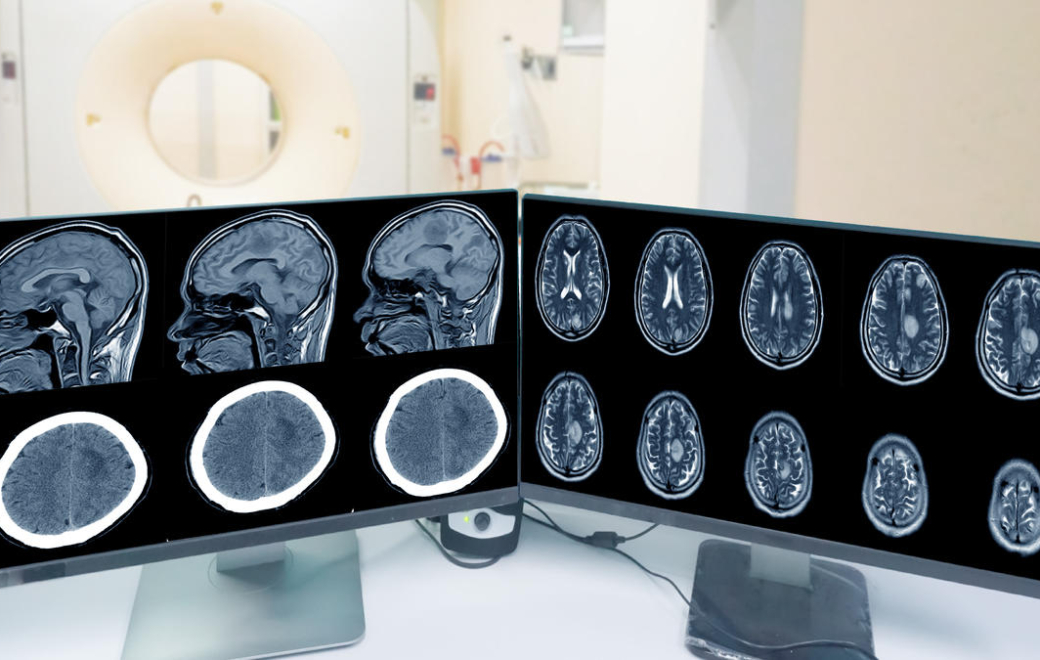

En ce qui concerne le dépistage du méningiome, près de 70 % des femmes et 50 % des hommes traités par la molécule en décembre 2021 avaient réalisé une IRM cérébrale, conformément aux recommandations de l’ANSM. Les chiffres sont moins bons à l’initiation de traitement avec moins de 50 % d’IRM, examen pourtant préconisé avant toute instauration de traitement.